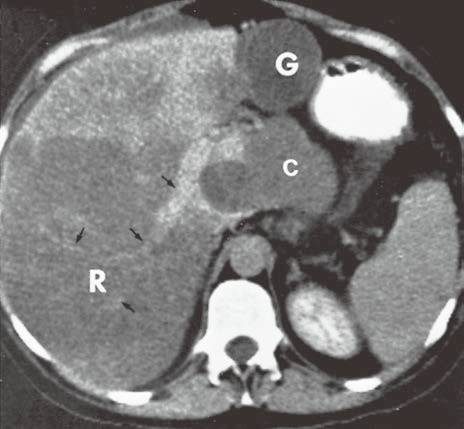

| 脂肪浸润(图1〜图 3) | 肝脏密度弥漫性减低。在肝脏脂肪变的低密度背景下,门静脉表现为高密度结构(平扫时正常门静脉呈低密度)。 | 由于三酰甘油过度沉积所致,见于肝硬化或其他肝脏疾病。正常肝脏平均CT值不低于脾脏,肝脏脂肪 浸润时CT密度较低。肝硬化引起脂肪浸润,伴有肝右叶萎缩,尾状叶体积增大。 |

图1肝硬化患者的肝内脂肪浸润

图3肝硬化再生结节